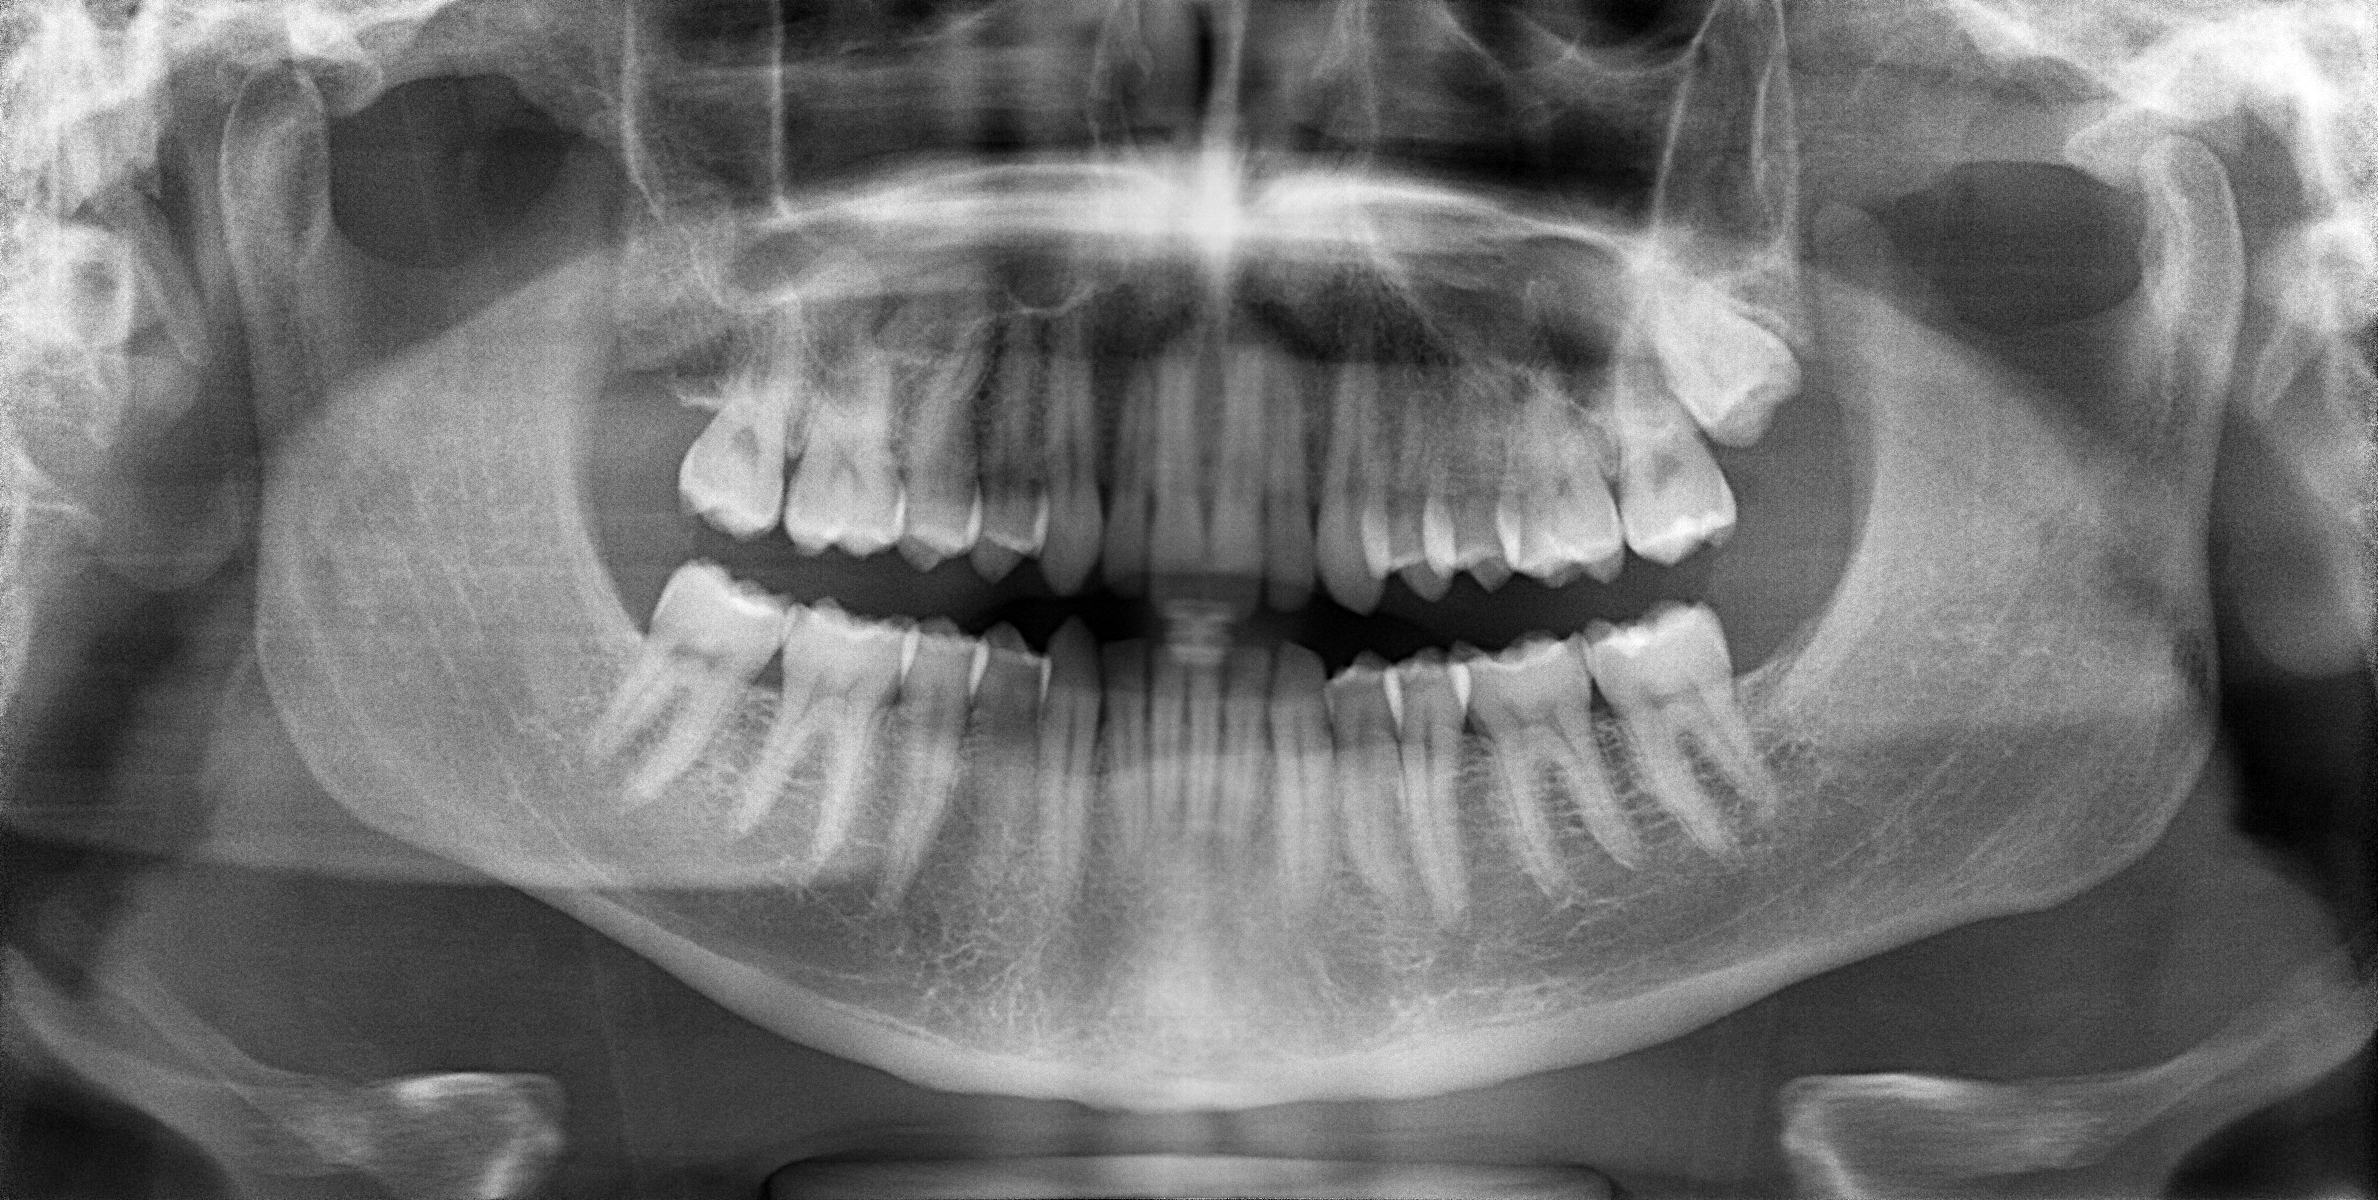

初診時には、デンタルドックという精密検査を行い、MRI撮影(左右)、レントゲン、口腔内写真などを確認しましたが、歯科的な問題は咬み合わせ以外には見られませんでした。

診断、治療計画の中ではMRI画像から軟骨が前方にずれているのが唯一確認出来ます。

術前のT-scanで、咬み合わせとしては奥歯に力が偏っているのが確認できます。しかし、患者さんご本人にはその違和感や症状を自覚されていませんでした。

T-scan による検査を行ったことで、咬み合わせに問題があることがわかりましたが、その他の検査では異常は見られませんでした。